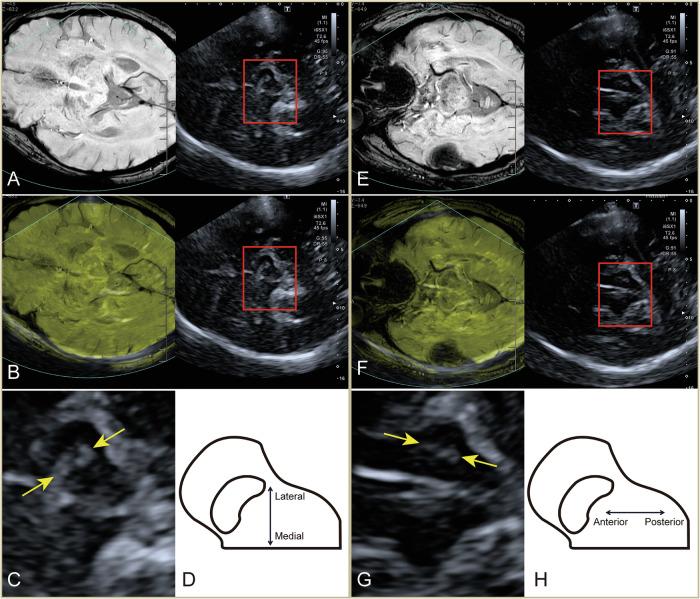

Substantia nigra hyperechogenicity (SNH) assessed by transcranial sonography (TCS) is a neuroimaging biomarker of Parkinson's disease (PD), but its actual location and spatial changes are poorly understood. We aimed to evaluate the location and spatial progression of SNH in PD utilizing TCS-MR fusion imaging. This prospective study enrolled eighty-four PD patients and sixty-two controls. The plane with the largest area of red nucleus, the plane with the largest area of SNH, and the plane where the red nucleus is just out of view were selected and segmented, respectively, and echogenicity indices were calculated. SNH could present in SN, dorsal band of SN, red nucleus, and ventral tegmental area, and had two orientations. In the left midbrain, the anterior-posterior orientation had longer disease duration, larger SNH area, and higher Hoehn-Yahr stage than medial-lateral orientation. The anterior-posterior orientation and accumulation in various nuclei of SNH may serve as promising neuroimaging markers for PD progression.

经颅超声检查(TCS)评估的黑质高回声(SNH)是帕金森病(PD)的一种神经影像生物标志物,但其实际位置和空间变化尚不清楚。我们旨在利用TCS-MR融合成像评估PD中SNH的位置和空间进展。这项前瞻性研究纳入了84例PD患者和62名对照。分别选择并分割红核面积最大的平面、SNH面积最大的平面以及红核刚不可见的平面,并计算回声指数。SNH可出现在黑质、黑质背带、红核和腹侧被盖区,且有两种方向。在左中脑,前后方向的病程更长、SNH面积更大、Hoehn-Yahr分期更高,比内外侧方向明显。SNH的前后方向及在各核团中的积聚可能是PD进展的有前景的神经影像标志物。